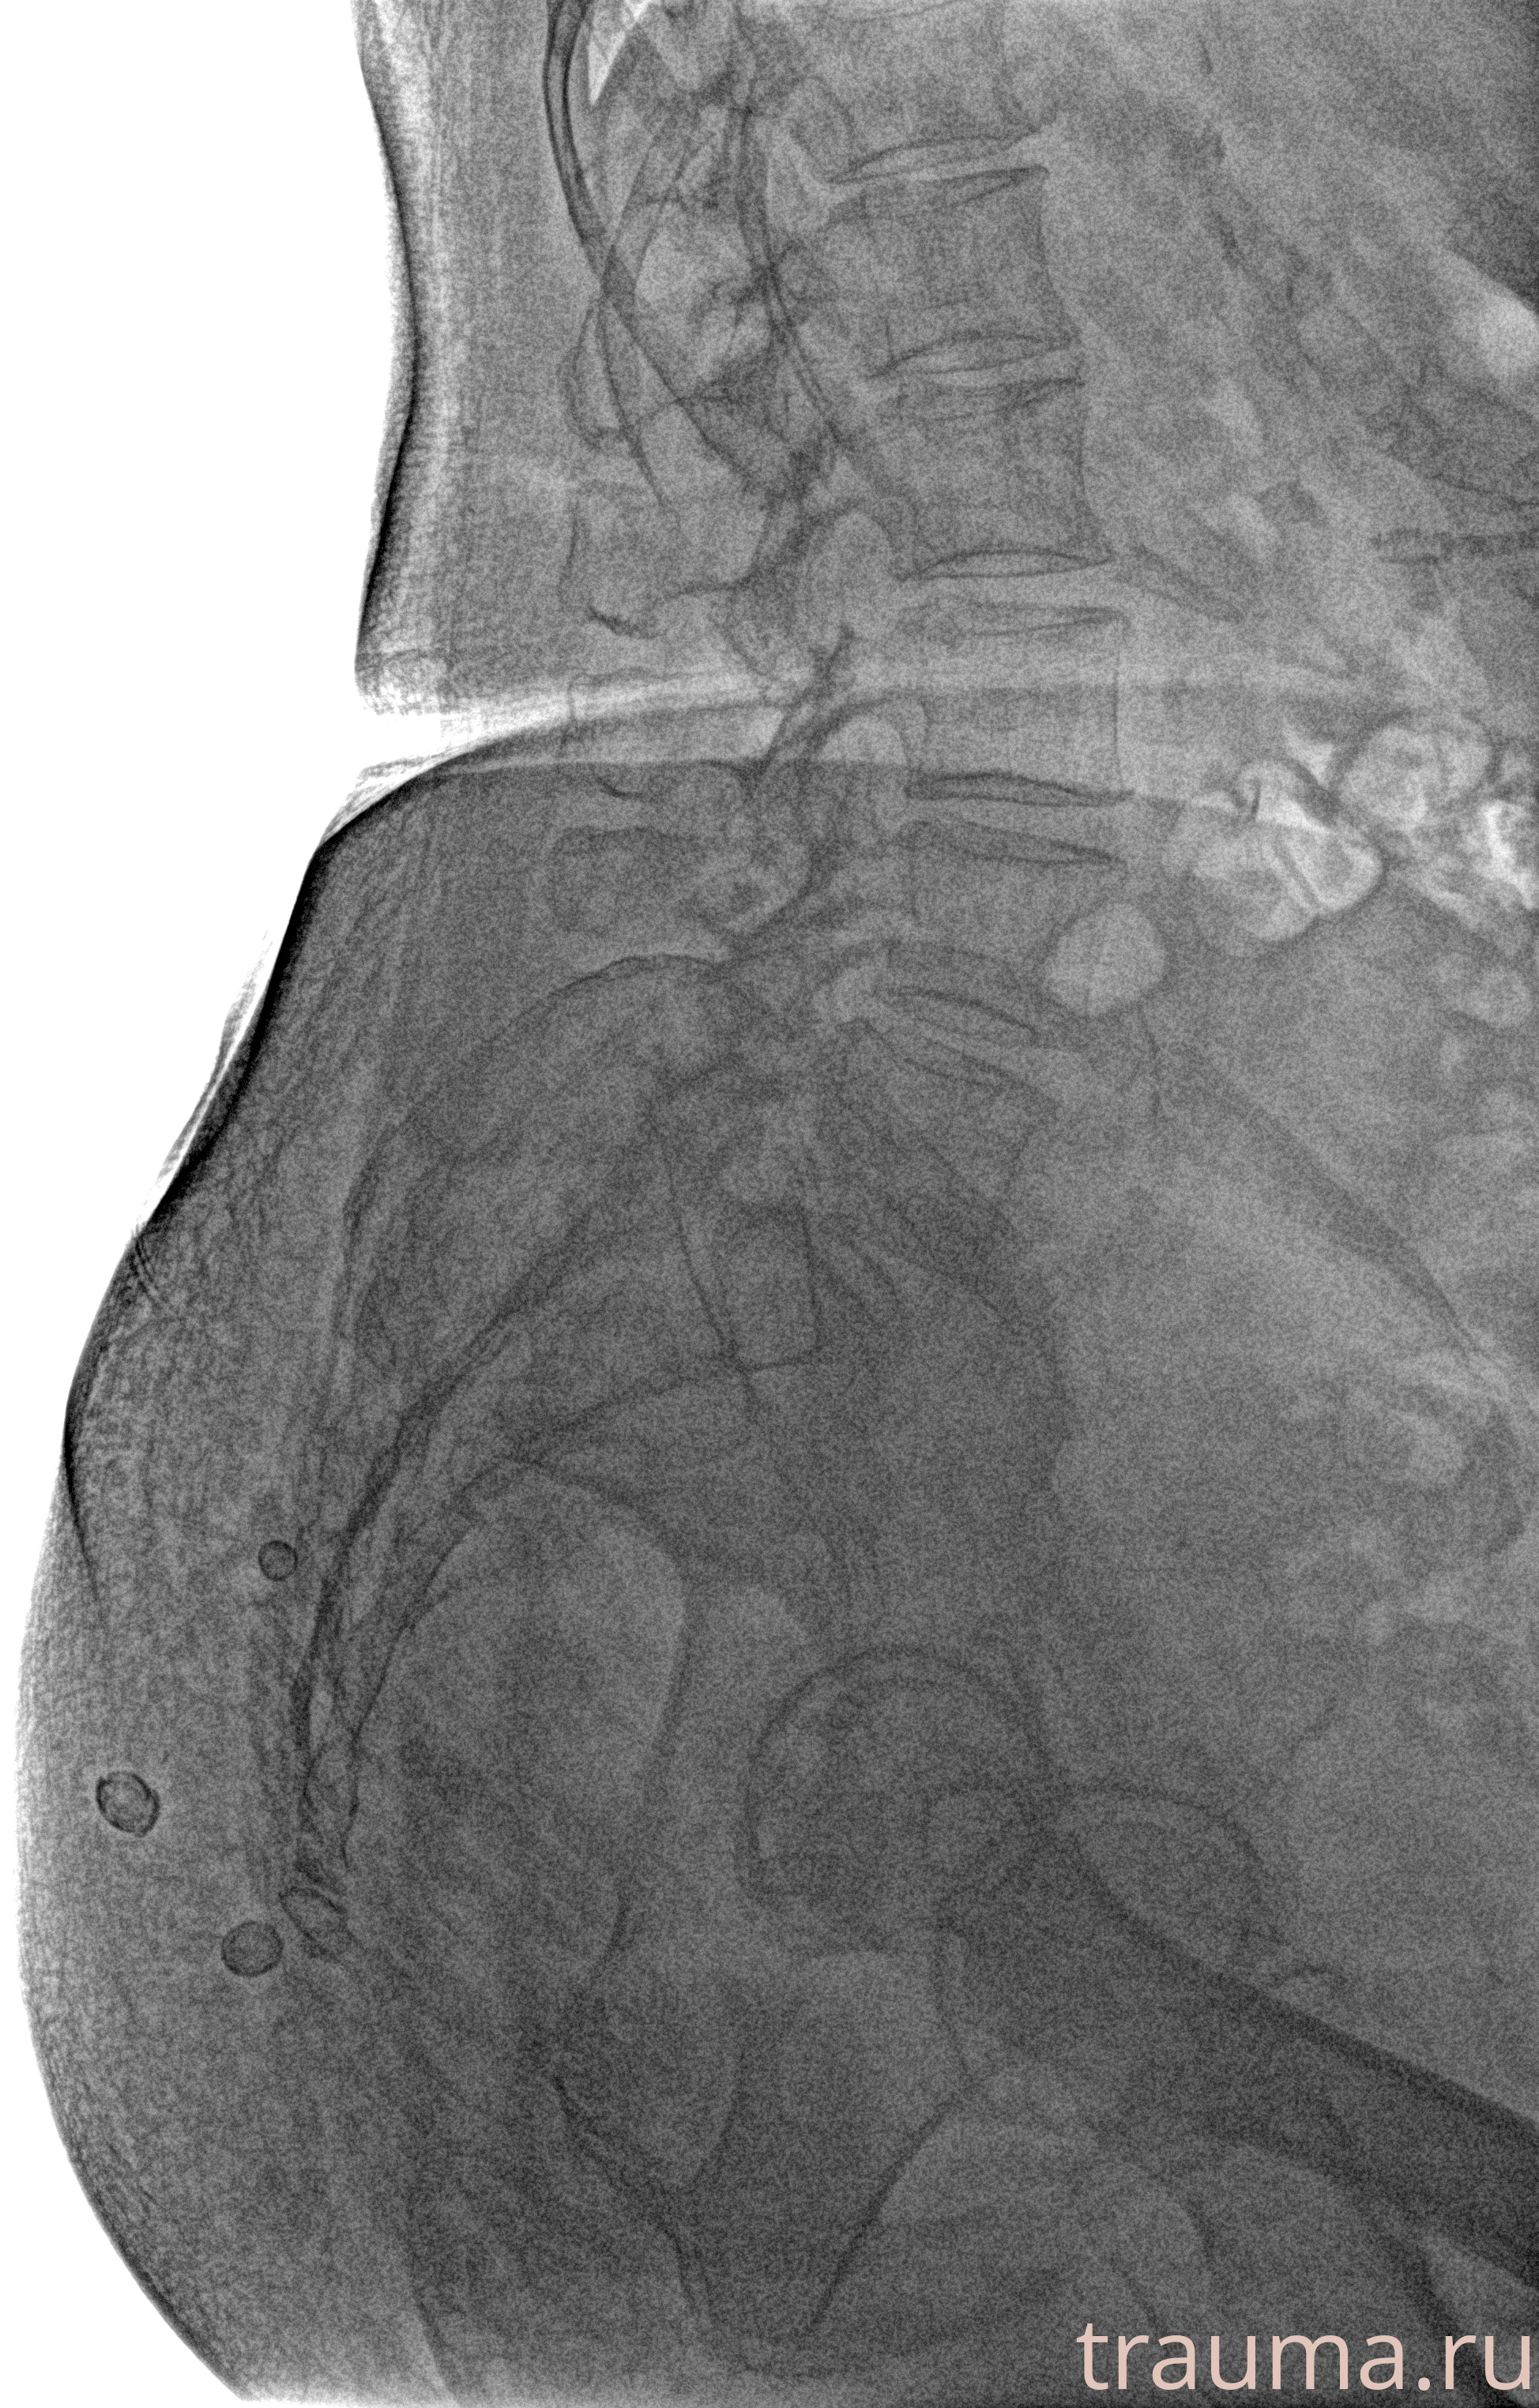

Рентгенограммы

Рентген на дому: по вашему адресу приезжает врач-рентгенолог, травматолог-ортопед с мобильным рентгеновским аппаратом, проводит диагностику травмы или заболевания, делает необходимые рентгенограммы, дает рекомендации по дальнейшему лечению. Получить качественные снимки в домашних условиях возможно благодаря уникальной методике, разработанной МосРентген Центром для института  Склифосовского